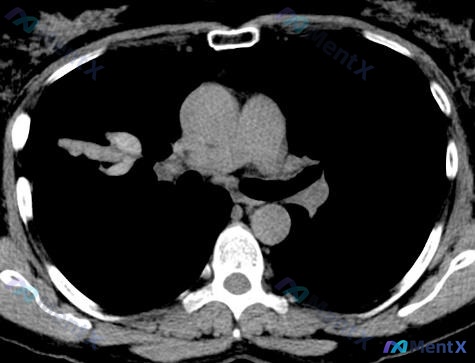

整理了一份很有意思的胸部CT读片病例,常规思路很容易被带偏,分享一下我的分析逻辑。 --- 先看完整影像表现 这份CT的肺窗+纵隔窗给出的信息很明确,也很有迷惑性: 【阳性征象】 1. 右肺门/上叶前段:类结节/团块状实性高密度影,边缘有毛刺,周围轻微纤维条索牵拉胸膜 2. 纵隔窗:病变与周围血管界...